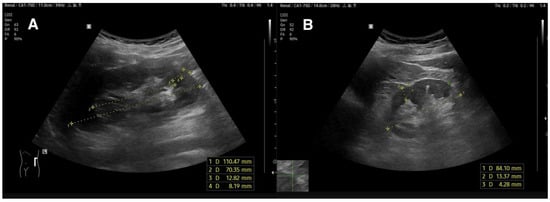

3.1.2. Renal Length

3.1.3. Cortical and Parenchymal Thickness

3.1.4. Echogenicity